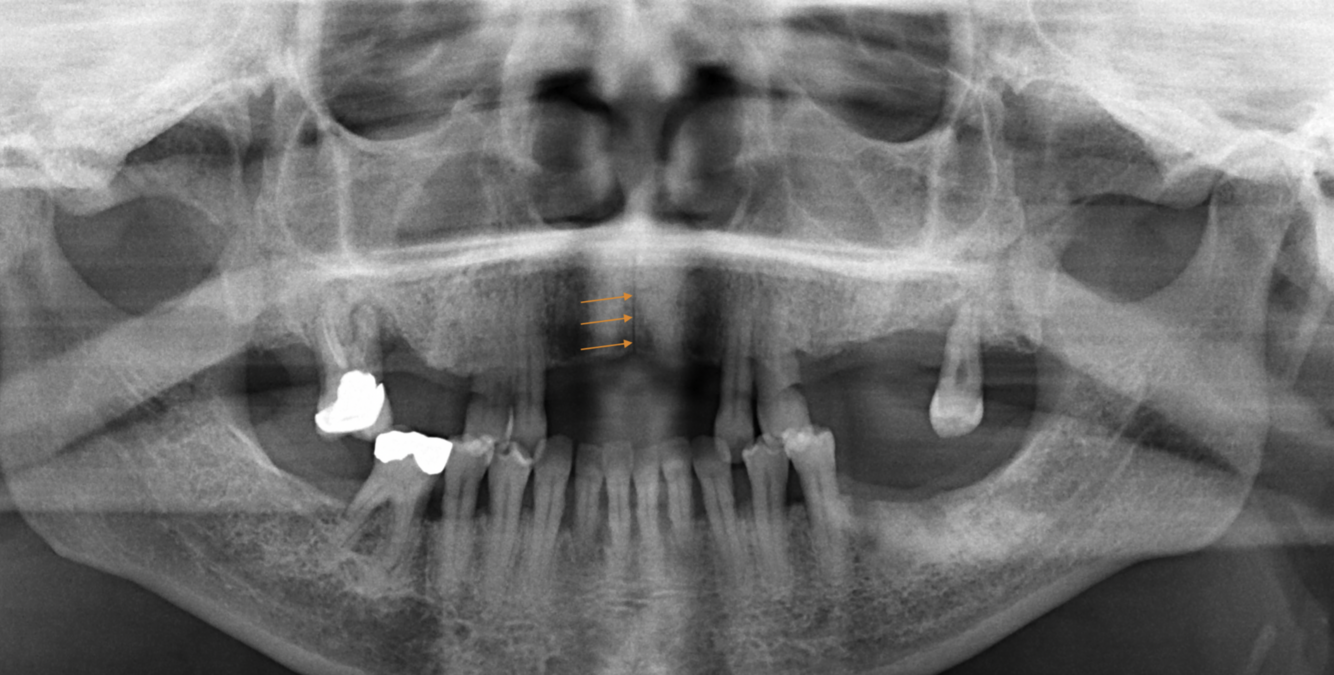

What does the orange indicate in the following image?

Submandibular gland fossa